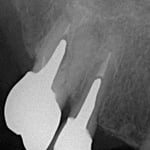

#穿孔修復

”穿孔”とは、簡単に言えば、歯の中に異常な”穴”が開いていることです。通常なら明らかに抜歯と診断されても不思議ではない症例ですが、時間をかけて修復しました。奥は他院で行ったインプラントですが、問題なく機能しています。

治療期間:約6ケ月

治療回数:11回(1~2回/月)

治療費:30万円(穿孔修復+根管治療+支台築造+セラミックス・クラウン)※毎回の処置料は別途

リスク:再治療は困難なこと。

(そもそも抜歯の症例)

※この症例はのちに、根管外から穿孔部を再封鎖しました。

治療後2.5年経過しました。(2022年4月04日時点)

力及ばず、残念ながら、2023(R5)年4月 抜歯になりました。